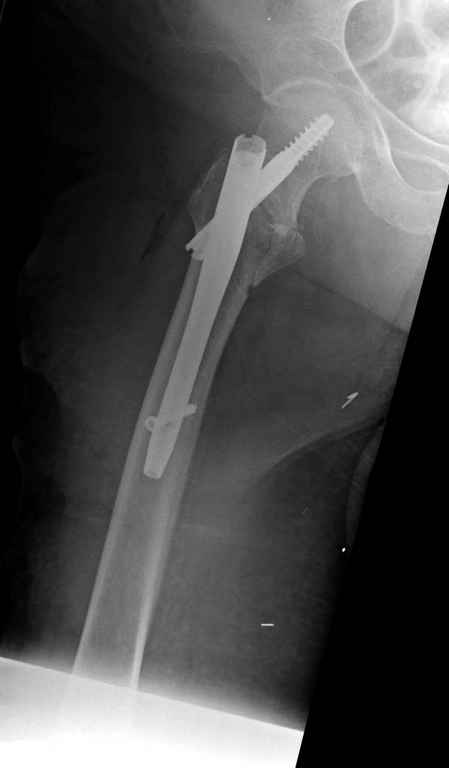

Диаметр гаммы в диафизарной части ~11 мм. А диаметр канала, тем более у пожилых с остеопорозом, может быть мм 15. Даже рассверливать обычно не приходится, после формирования широкого канала в вертельной области можно сразу толкать гвоздь, он влетает, как карандаш в стакан. Так что соответствия диаметров не бывает никогда. Однако представленная ситуация случается далеко не каждый раз. Если гвоздь в центральном отломке входит чуть медиальнее верхушки вертела, и идет вдоль передне-латеральной стенки центрального отломка, то все будет хорошо.

В приложении похожий пример, к счастью, пациентка появилась не после, а "за полчаса" до протрузии. Пересинтезировали с исправлением ошибок.